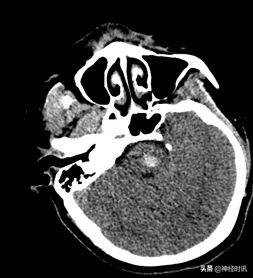

CT检查

脑干可见片状高密度影,测其最大层面约18 mm×15 mm× 20 mm,CT值约65 HU。脑室系统未见明显扩大及变形,脑沟脑裂显示清,中线结构居中。结合CT计算脑干出血量约3 ml。

急诊CT